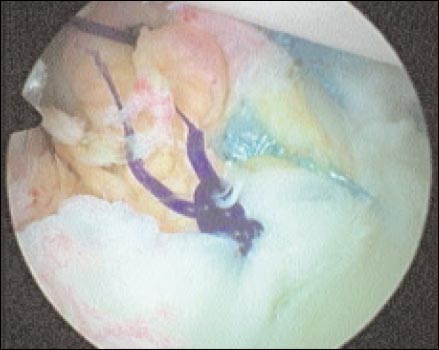

Los anclajes óseos son colocados en la unión oteocartilaginosa (Fig. 5) sobre el cartílago en tres puntos, aproximadamente correspondiente a horas 5, 4 y 2 (hombro derecho), dependiendo de la lesión; realizamos la toma capsular y del rodete con Ethibond Nº. 2, el pasaje de los hilos requiere de un “shutter-relay” o otros tipos de pasa-suturas. Utilizamos nudos deslizantes o no deslizantes según necesidad y, un empujanudos para llevar las estructuras capsulo-ligamentarias al sitio deseado.(Fig. 6). Con ambas técnicas realizamos plicaturas capsulares con los mismos puntos de la sutura transglenoidea o los anclajes óseos.

Figura 6: sutura con ancllajes oseos